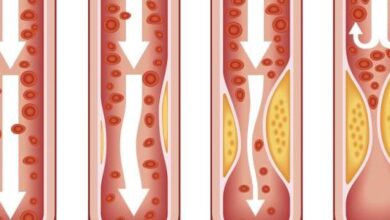

بالنسبة لأمراض الشرايين التاجيّة أو داء الشريان التاجيّ (بالإنجليزية: Coronary artery disease)، فإنّ الذبحة الصدريّة تُعدّ أكثر أعراض المرض شيوعًا، ويُعبّر عنها بالشعور بألم وضغط في الصدر أو ثقل أو حرقة فيه، إضفافةً إلى تنميل أو خدران غير طبيعي، كما يمكن أن يمتد الألم إلى أجزاء أخرى، مثل الكتف الأيسر، والذراعين، والرقبة، والفكين، والظهر، ومن الجدير بالذكر أنّ أمراض الشرايين التاجيّة قد تكون مصحوبة ببعض الأعراض الأخرى أيضاً،[٤] ومنها ما يأتي:[٤]

- التنميل، والضعف، والبرودة في الذراعين أو الساقين في حال تضيق الشرايين المسؤولة عن التروية الدمويّة فيها.